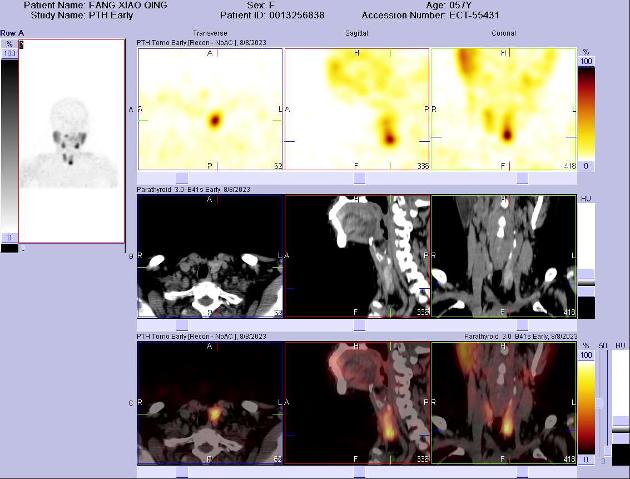

常用的顯像方法為99mTc-MIBI雙時(shí)相法。無(wú)需特殊準(zhǔn)備,盡量停用維生素D和鈣劑2周,檢查前無(wú)需禁食水。靜脈注射99mTc-MIBI后,于15分鐘和120分鐘采集早期和延遲顯像。為了更精確的定位及識(shí)別多發(fā)病灶,需要增加斷層融合顯像(SPECT/CT)。

病例2: 女52歲,無(wú)明顯誘因出現(xiàn)髖部疼痛,后查骨密度顯示重度骨質(zhì)疏松,給予“降鈣素+補(bǔ)鈣等”治療,癥狀好轉(zhuǎn)不明顯,再次就診查肌酐125 umol/L(參考值44-106 umol/L),鈣3.96 mmol/L(參考值2.11-2.52mmol/L),全段PTH: >2000.00pg/ml↑(參考值18.50-88.00 pg/ml)。甲狀旁腺平面及斷層融合顯像顯示:甲狀腺右葉下極后方占位伴放射性濃聚,考慮為功能亢進(jìn)的甲狀旁腺病變。手術(shù)切除,病理證實(shí)為甲狀旁腺腺瘤。